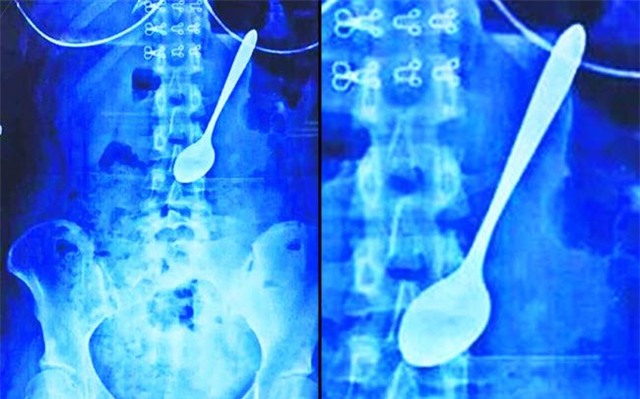

Một cô gái trẻ ở Trung Quốc đã vô tình nuốt cả chiếc thìa vào bụng trong khi ăn kem.